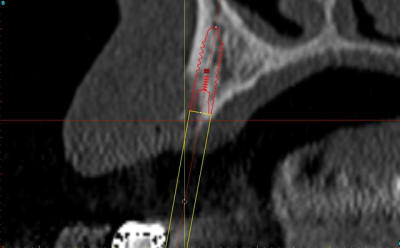

;Les photos:

1:

état initial,

disque diamanté

scie circulaire